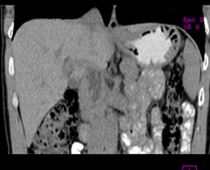

患者,男,57,常年不吃午饭,近一个月来腹部隐痛,无明显黄疸,明天进行增强扫描,图象另上传,麻烦各位帮忙一起看看讨论讨论

肝外胆管扩张,胰头增大,肠系膜上静脉似有包埋征象。

考虑:胰头占位性病变,建议增强进一步检查。

肝外胆管扩张,胰头增大,占位性病变可能性大.

肝内外胆管扩张,胆管未端阻塞,建议mri检查

肝外胆管稍扩张,胰腺钩突略增大,但外形尚可,境界清楚。(常年不吃午饭)提示胰腺炎可能大,肿瘤第二步考虑。

支持考胰头占位性病变,感觉十二指肠壁不规则增厚,不排除十二指肠降部占位可炎症

胰头增大,考虑胰头占位性病变。

胰头增大,胆总管增宽,考虑胰头癌可能性大,明天看增强片有助诊断.

单纯性胆总管扩张,下端梗阻.